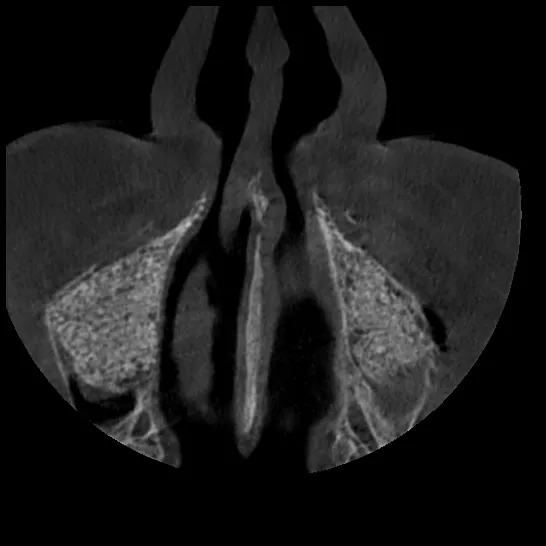

Figs. 60-62 Final panoramic radiograph showing the implant rehabilitation: BLX implants in the maxillary tuberosities and grafted sinus, BLC implants in the anterior maxilla, and TLX NT implants supporting the mandibular restoration. Note also the horizontal CBCT views demonstrating good integration and adequate anteroposterior (AP) spread of the implants.